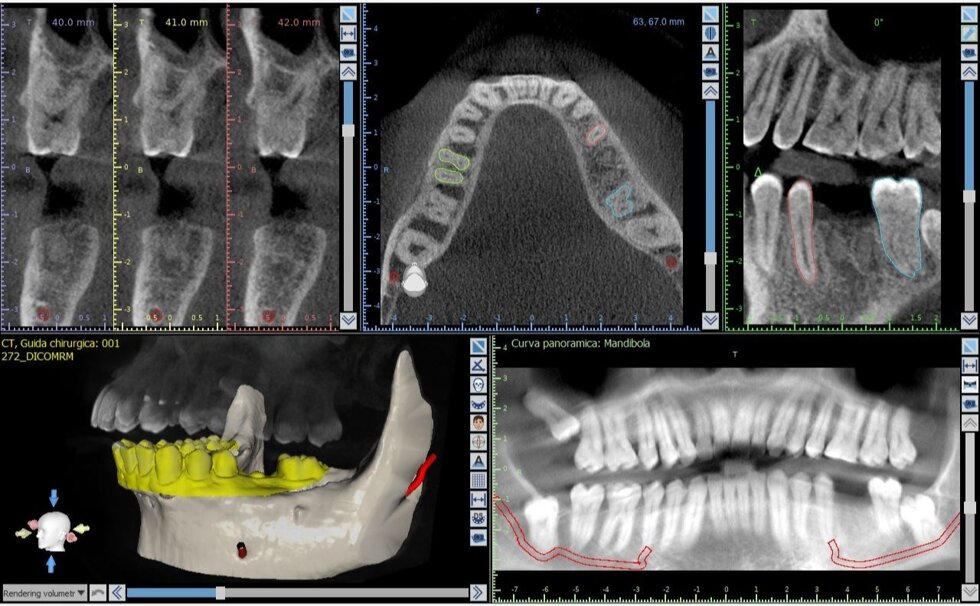

Il processo inizia con una tomografia computerizzata (CBCT), che fornisce un’immagine tridimensionale dettagliata delle arcate dentarie e delle strutture ossee. I dati vengono importati in software dedicati, dove il chirurgo può pianificare virtualmente l’intervento: scegliere la posizione, l’inclinazione e la profondità ottimali di ciascun impianto, valutando anche la densità ossea e la distanza da nervi o seni mascellari.

Una volta definito il piano chirurgico, si procede alla realizzazione di una dima chirurgica personalizzata, ottenuta tramite stampa 3D. Questa mascherina guida gli strumenti del chirurgo durante l’intervento, consentendo di inserire gli impianti nella posizione esatta prevista dal progetto digitale, senza necessità di ampie incisioni gengivali.